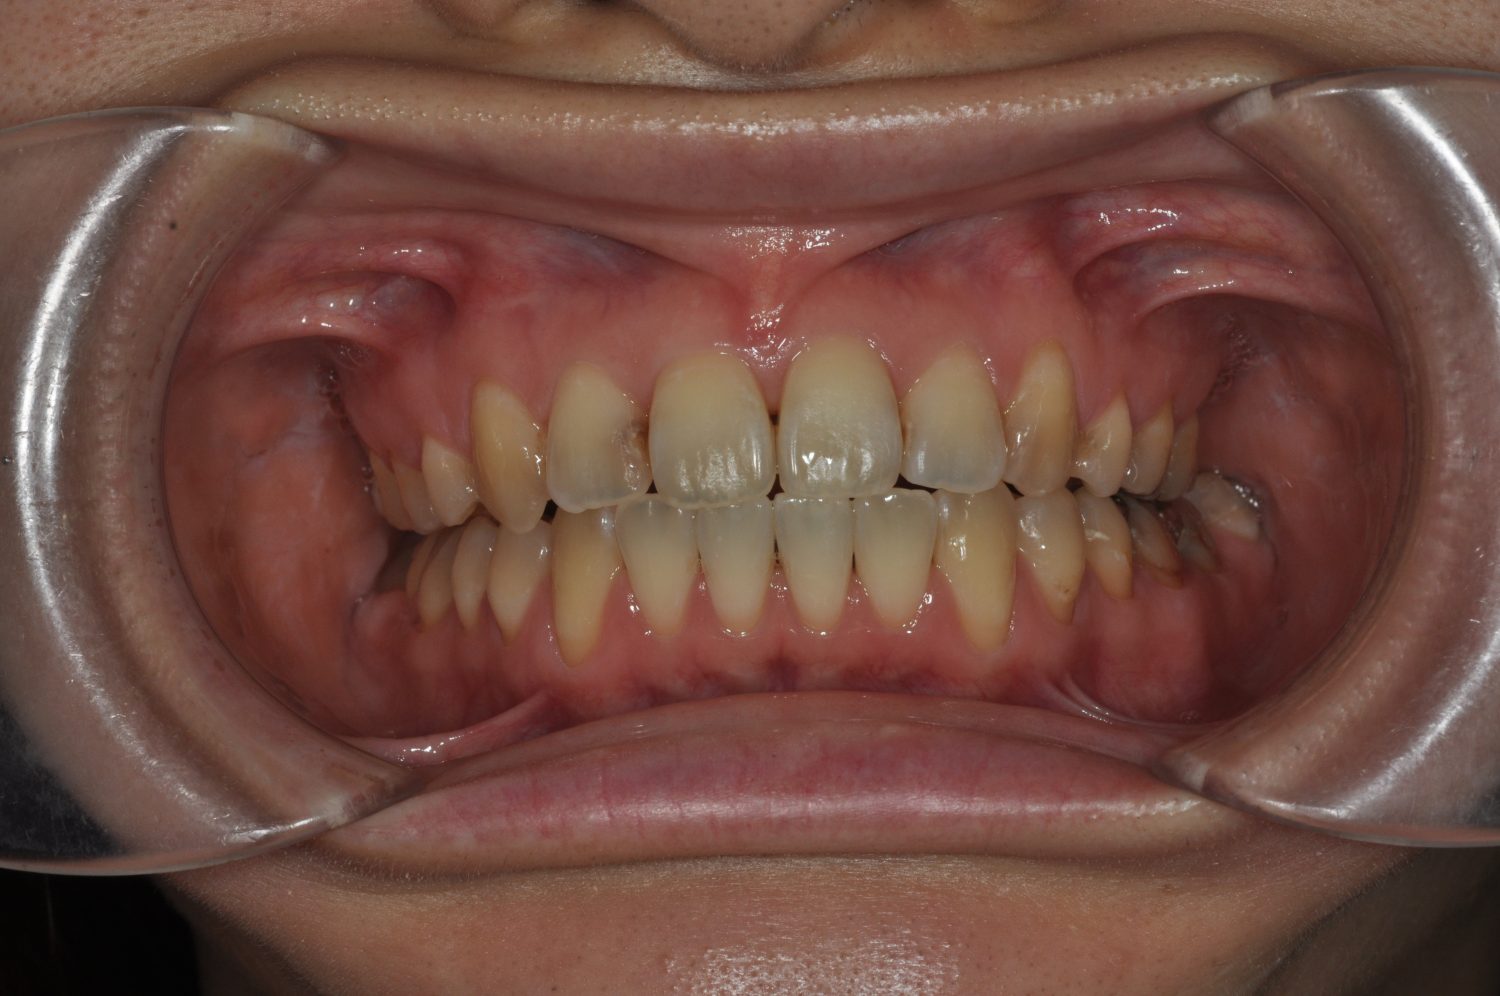

| 主訴 | 前歯の出っ歯を直したい |

| 治療内容 | 上下顎とも標準範囲であるが、上下顎前歯ともに唇側傾斜による、上下顎前突。上顎小臼歯を抜去し配列を行うこととした。 |

| 治療費 | Ⅱ期治療費:770,000円 (税込) 調整料 5,500円 (税込)×23回 保定時:22,000円 (税込) 計 918,500円 (税込) |

| 治療期間 | 2年1ヶ月 |

| 治療回数 | 25回 |

| 想定されたリスク | 矯正器具の装着に伴い、むし歯や歯周病のリスクがありました。また、歯根吸収や歯肉退縮のリスクもありました。 |

上下顎前歯の唇側傾斜による上下顎前突。オーバージェットが大きいため、上顎のみの抜歯で配列を行った。